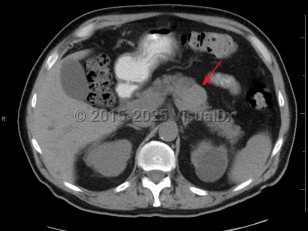

Acute pancreatitis

Chronic pancreatitisChronic pancreatitis

Pancreatic carcinomaPancreatic carcinoma